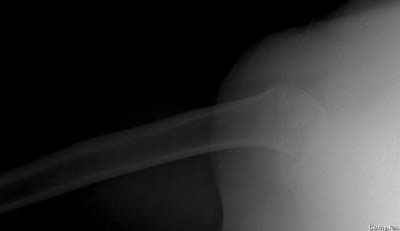

Здесь случай перелома-вывиха плеча, больному 56 лет, после "дважды" закрытой неудачной репозиции, опять же ургентно взяли в операционную, после полного общего обезболивания попытались сделать репозицию, и фиксацию провели спицами.

Больной находился в повязке, примерно напоминяющей косыночную, рекомендованы движения в локтевом суставе и маятниковые движения в плече, спицы удалены в три недели (были случаи миграции)

Больной амбулаторный, предупрежден на случай осложнения АВН головки.